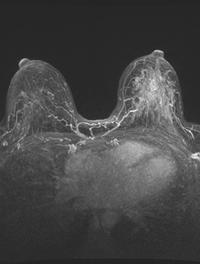

Depuis plus de 40 ans, de nombreuses études ont montré qu’une chirurgie mammaire conservatrice associée à une radiothérapie adjuvante [...]